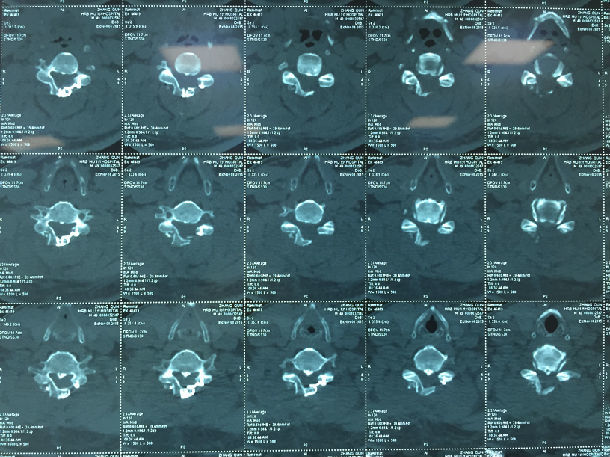

手术前-多节段颈椎间盘突出/黄韧带肥厚/颈椎管狭窄-脊髓损伤

显微镜下经颈后路行单开门椎管扩大成形术-颈椎管明显增宽/脊髓受压解除/患者逐渐康复